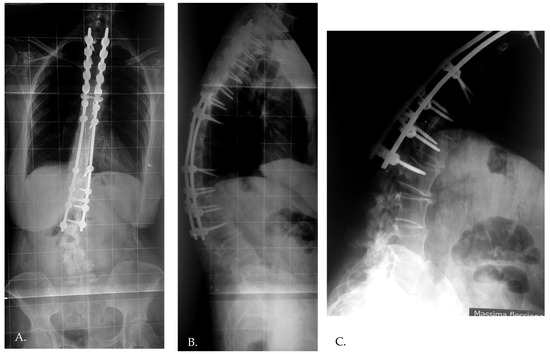

Figure 1. Standing preoperative (A,C) X-rays and immediate postoperative X-rays (B,D) of a 23 years old female patient.